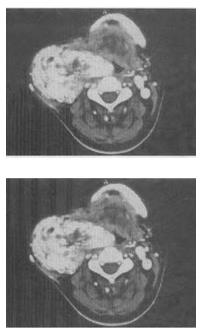

男,45岁,颈部渐进性增大包块,CT增强扫描如图所示,最可能的诊断是()。

A:颈部肿大淋巴结

B:颈动脉夹层

C:神经鞘瘤

D:颈动脉体瘤

E:甲状腺癌